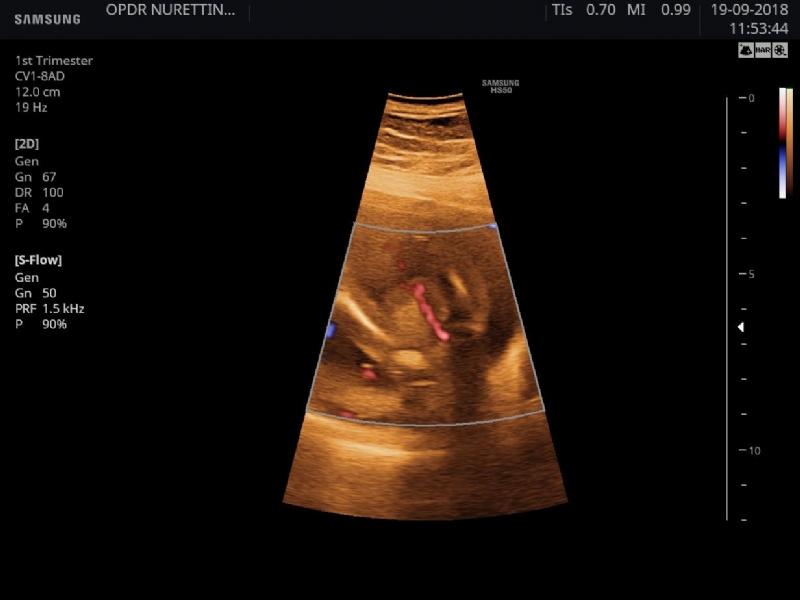

GÖBEK KORDONUNDA TEK ARTER TEK VEN |

![]() |